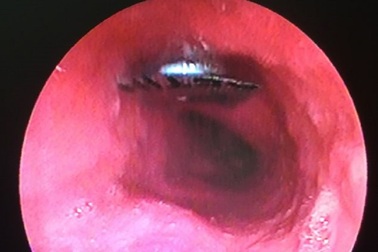

Viên thuốc còn nguyên vỉ đóng ngang thực quản bệnh nhânSơ ý khi uống thuốc, nữ bệnh nhân quên lột bỏ vỉ nên bị dị vật đóng ngang thực quản phải nhập viện cấp cứu. Vết thương tuy không phức tạp nhưng đặc biệt nguy hiểm, có thể gây nhiễm trùng trung thất dẫn tới tử vong.

Quên bóc vỉ thuốc trước khi uống, nữ bệnh nhân 65 tuổi phải nhập việnBị sốt, một nữ bệnh nhân tại Quảng Bình đã mua thuốc về uống, tuy nhiên khi sử dụng đã quên bóc vỉ và nuốt luôn vào bụng. Người này sau đó đã phải nhập viện để gắp viên thuốc còn nguyên vỏ ra ngoài.